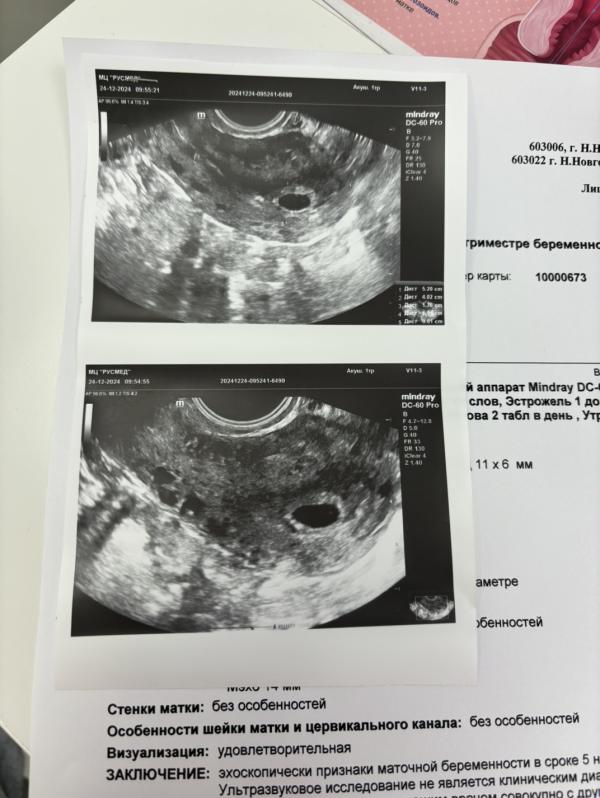

Перенос от 5.12: когда ждать эмбрион и сердцебиение? Обсуждаем после новогодних праздников

Перенос от 5.12 , ждём после нового года увидеть эмбрион и сб